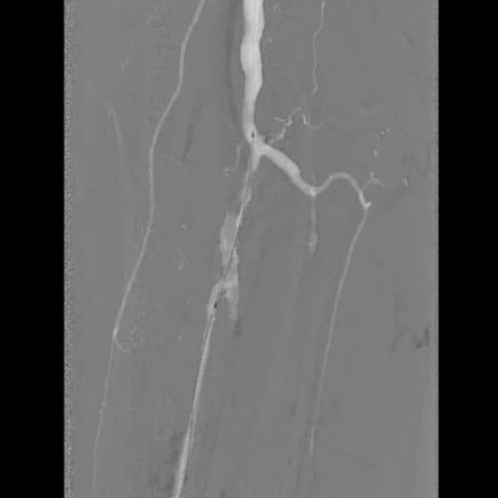

铁基可降解支架植入

按计划植入3×38mm载药铁基可降解支架,准确定位以完全覆盖病变;采用8 atm压力球囊扩张释放支架,确保支架充分张开。

术后评估

造影显示:胫腓干动脉血流恢复通畅,支架形态及位置理想,胫后动脉显影较术前明显改善;

腔内超声证实:铁支架完全张开、贴壁良好,无明显残余狭窄。